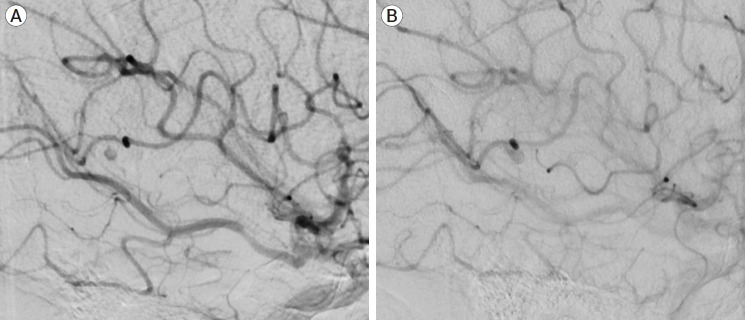

Aneurysms of the pineal region are rare and theoretically could arise from the medial posterior choroidal artery (MPChoA) or lateral posterior choroidal arteries (LPChoA). A 64-year-old lady with subarachnoid haemorrhage (SAH) and intraventricular haemorrhage (IVH) due to a ruptured MPChoA aneurysm was treated with microsurgical aneurysm excision via an occipital interhemispheric approach. This case demonstrates the importance of being mindful of rare aneurysm locations when initial vascular imaging in SAH appears normal.

松果体区域的动脉瘤是罕见的,理论上可能起源于内侧后脉络膜动脉(MPChoA)或外侧后脉络膜动脉(LPChoA)。一位64岁的女性因MPChoA动脉瘤破裂而出现蛛网膜下腔出血(SAH)和脑室内出血(IVH),经枕半球间入路行显微手术切除动脉瘤。本病例表明,当SAH的初始血管成像显示正常时,注意罕见动脉瘤位置的重要性。